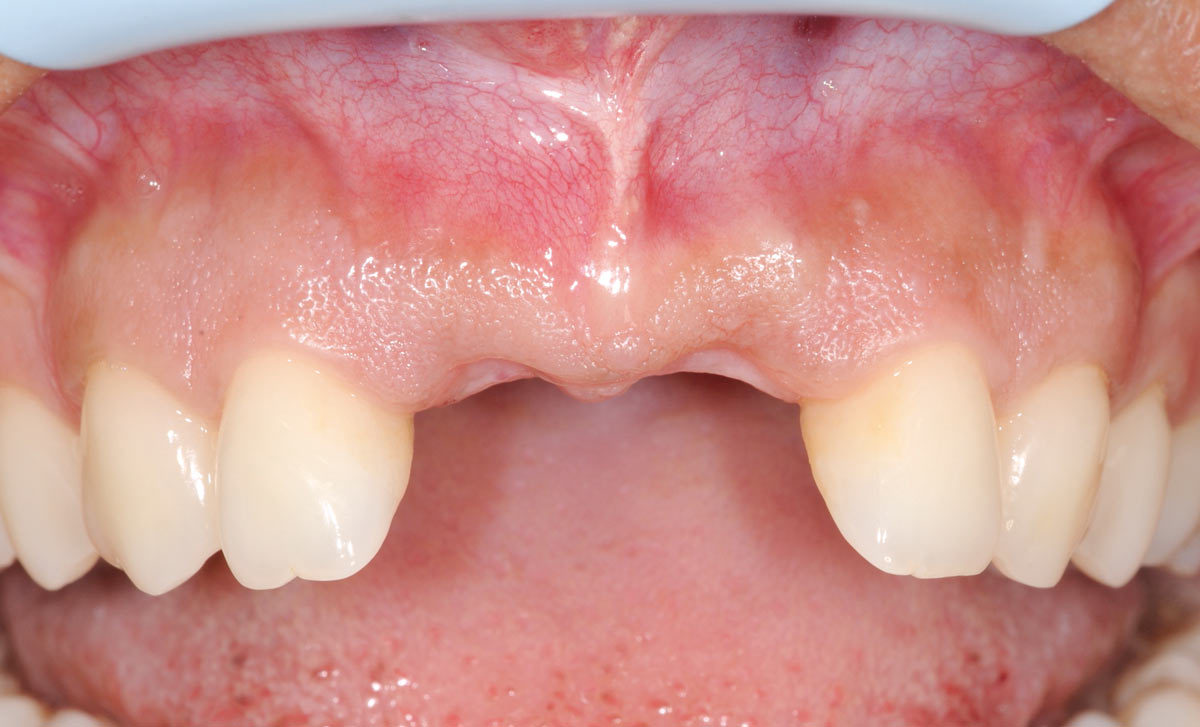

Initial situation: bone loss due to lack of physical load of bridge retained region 11

Initial situation pre-op: Central incisors with mobility 3